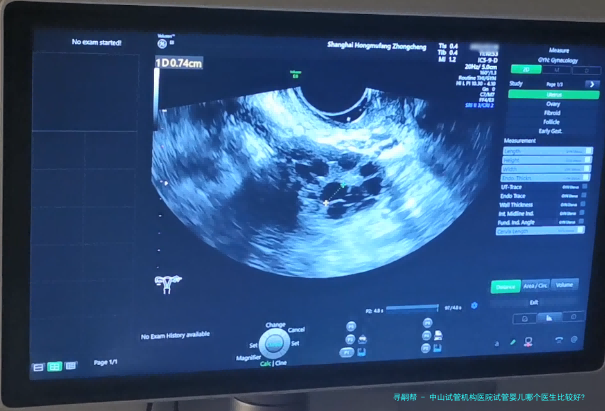

中山试管婴儿机构医院的试管婴儿移植过程严格遵循规范,旨在最大程度地提升成功率。具体过程如下:

胚胎培养:将促排卵后的卵子和精子在实验室进行受精和培养,待胚胎发育到5-8个细胞期后进行移植评估。 宫颈检查:使用超声刀对宫颈进行观察和检查,确保宫颈健康状况良好。 胚胎移植:将优质胚胎经阴道或子宫腔内种植到女性子宫内。 移植后恢复期:患者需保持充分休息,避免剧烈运动和性生活,并接受药物治疗以提高妊娠成功率。中山试管机构医院凭仗雄厚的医疗力量、先进设备和专业的医护团体,专心于为每一位病患提供优质的试管婴儿服务。要是您正进行考虑寻求试管婴儿治疗,建议您咨询中山试管机构医院相关专业人士,取得更详细的信息和个性化的方案。